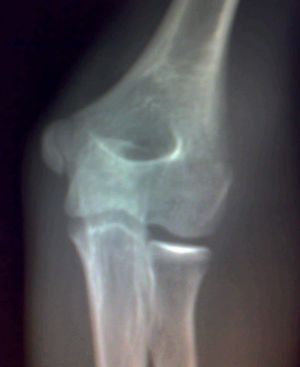

影像所见:左肱骨远端隐约可见自外上髁向髁间走行不规则骨质透亮线,侧位显示肱骨前线欠光整。未见脱位征象。骨骺发育未见异常。

印象:左肱骨远端骨折不除外。

我怎么感觉肱骨外上髁上方皮质有裂隙啊,建议一周后复查。

是内上髁正常存留骺影

加照对侧,感觉肱骨外上髁上方内侧骨骺旁显示低密度负影。

外上髁骨折?

是内上髁正常存留骺影,支持